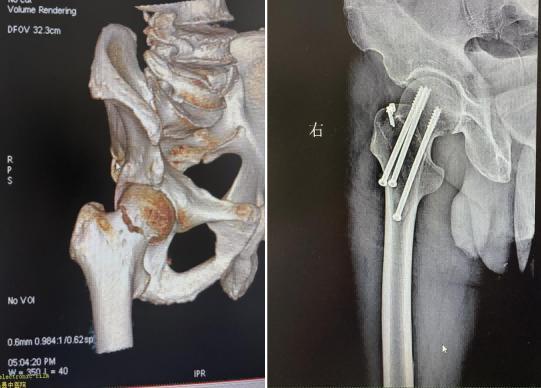

78岁的李爷爷则因不慎摔倒导致股骨颈骨折,考虑到老年患者身体耐受度低,团队实施闭合经皮空心钉内固定术:在C型臂引导下精准定位,通过3个微小切口植入空心钉,手术耗时仅40分钟。术后配合康复指导,有效降低了老年患者长期卧床引发的并发症风险。